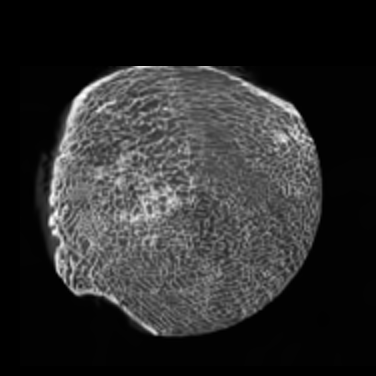

Figure 4: Visual comparsion of SRCT Case 111 from the Tibia dataset. The restored bony structures are shown in the red and yellow boxes in Fig. 5. The display window is [-900, 2000] HU.

III-D Experimental Results with the Tibia Dataset

We evaluated the proposed algorithms against the state-of-the-art algorithms on the tibia dataset. We present typical results in Fig. 4. It is observed that BM3D can effectively remove the noise, but it over-smoothens the noisy LR images. Then, the interpolation-based methods (NN+, Bilinear+, Bicubic+, Lanczos+) yield noticeable artifacts caused by partial aliasing. On the other hand, the DL-based methods suppress such artifacts effectively. It can be seen that our proposed GAN-CIRCLE recovers more fine subtle details and captures more anatomical information in Fig. 5. It is worth mentioning that Fig. 4 shows that there are severe distortions of the original images but SRGAN generates compelling results in Figs. 6-8, which indicate VGG network is a task-specific network which can generate images with excellent image quality. We argue that the possible reason is that the VGG network [68] is a pre-trained CNN-based network based on natural images with structural characteristic correlated with the content of medical images [80]. Fig. 5 presents that the proposed GAN-CIRCLEs can predict images with shaper boundaries and richer textures than GAN-CIRCLE, and GAN-CIRCLEu which learns additional anatomical information from the unpaired samples. The quantitative results are in Table II. The results demonstrate that the G-Forward achieves the highest scores using the evaluation metrics, PSNR and SSIM, which outperforms all other methods. However, it has been pointed out in [81, 82] that high PSNR and SSIM values cannot guarantee a visually favorable result. Non-GAN based methods (FSRCNN, ESPCN, LapSRN) may fail to recover some fine structure for diagnostic evaluation, such as shown by zoomed boxes in Fig. 5. Quantitatively, GAN-CIRCLE achieves the second best values in terms of SSIM and IFC. It has been pointed out in [83] that IFC value is correlated well with the human perception of SR images. Our GAN-CIRCLEs obtained comparable results qualitatively and quantitatively. Table II shows that the proposed semi-supervised method performs similarly compared to the fully supervised methods on the tibia dataset. In general, our proposed GAN-CIRCLE can generate more pleasant results with sharper image contents.